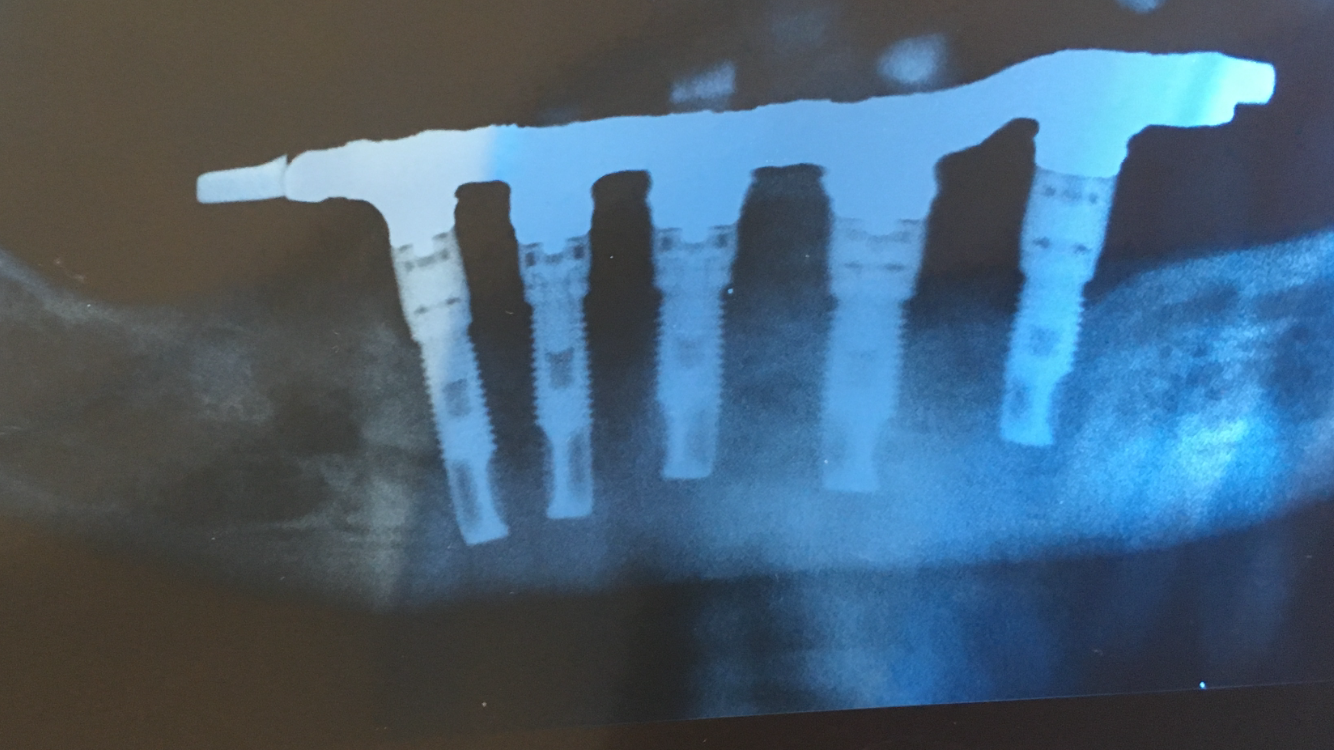

Buenas tardes: presento un caso de un paciente que le colocaron hace unos 15 años implantes y rehabilitaron con una híbrida. La clínica donde se lo realizaron ha desaparecido. Paciente [...]